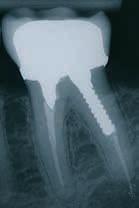

Klik ind på Tandlægebladet.dk og opret en reklamation, så sørger vi for, at bladet lander i din postkasse.

Klik ind på Tandlægebladet.dk og vælg om os

BAGGRUND – Transverselle okklusionsafvigelser kombineret med en vækstbetinget kæbedeformitet korrigeres sædvanligvis ved en sektioneret Le Fort 1-osteotomi eller kirurgisk assisteret ganeekspansion. Ved ekstreme transverselle skeletale diskrepanser mellem maksillen og mandiblen kan der være indikation for transversel udvidelse af mandiblen ved hjælp af mandibulær midtlinjeosteotomi eller mandibulær midtlinjedistraktionsosteogenese.